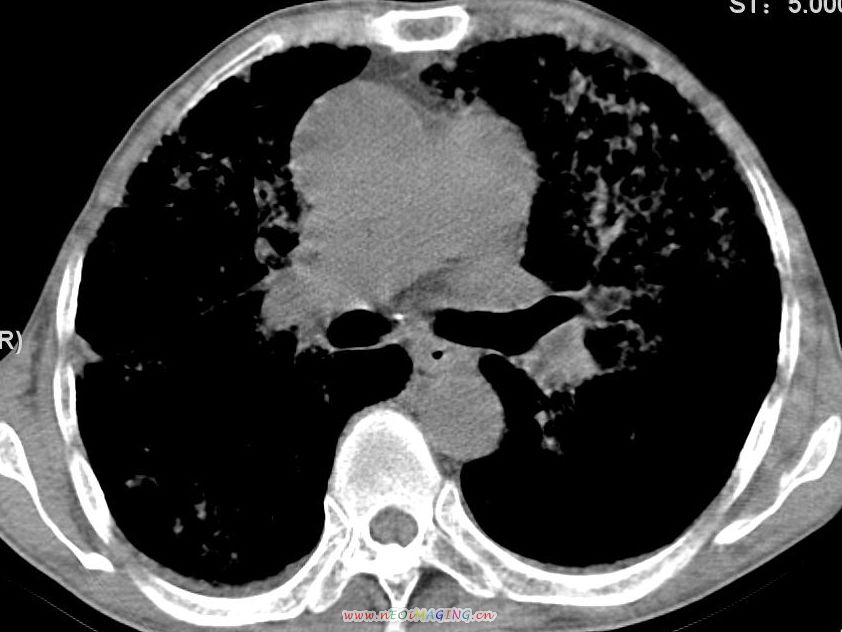

患者咳嗽月余,高热数天,咳黄色稍脓痰。

高热数天,咳黄色稍脓痰,肯定应该有急性化脓性感染,左上叶舌段及右肿叶可见多量斑片状及支气管气像,首先考虑肺部感染合并血型播散性肺脓肿(脓肿为早期改变),其次不排除有肺泡癌,第三不排除结核,建议治疗后复查

双肺野分布多个小结节状高密度影,其内散在斑片状模糊影,气管。支气管通畅,纵隔内淋巴结钙化,胸膜局限性增厚粘连,胸腔少量积液。结合病史考虑结核并感染的可能性大,胸膜炎并积液。肺泡癌待排。

亚急性血行播散型肺结核合并肺内感染

纵隔内见钙化的淋巴节,上肺见钙化灶,双肺均匀弥漫分布小结节影,边缘较清楚,能不能考虑是在矽肺的基础上并发的结核和感染,请详细了解病史结合临床.